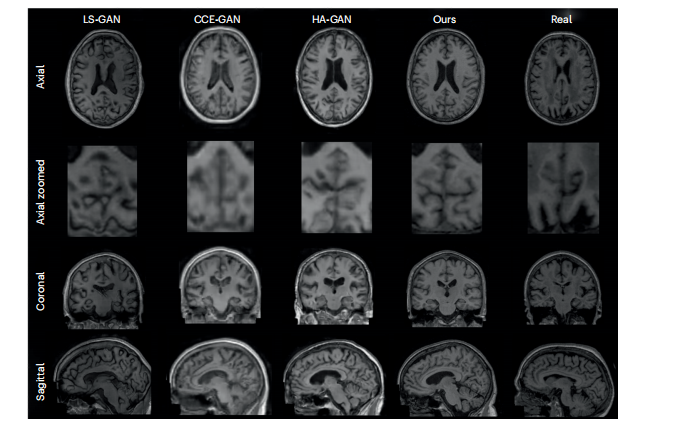

Fig. 2 | Random synthetic samples from ADNI dataset. Random synthetic samples from the LS-GAN, CCE-GAN and HA-GAN baseline trained on ADNI together with our proposed model trained on ADNI and the a real participant from the datasets. All three planes of visualization (axial, coronal and sagittal) are presented. Additionally an axial zoomed in visualization of the cerebellum is showcased due to the higher number of cortical folds entailing more highfrequency details. All the visualization planes are from the same synthetic samples and real participant.

图2 | 来自ADNI数据集的随机合成样本。显示了从LS-GAN、CCE-GAN和HA-GAN基线模型(在ADNI数据集上训练)生成的随机合成样本,以及我们提出的模型在ADNI数据集上训练生成的样本和数据集中一位真实参与者的样本。所有三个可视化平面(轴状、冠状和矢状)均已展示。此外,还展示了小脑的轴向放大可视化,因为小脑具有较多的皮层褶皱,包含更多高频细节。所有可视化平面均来自相同的合成样本和真实参与者。